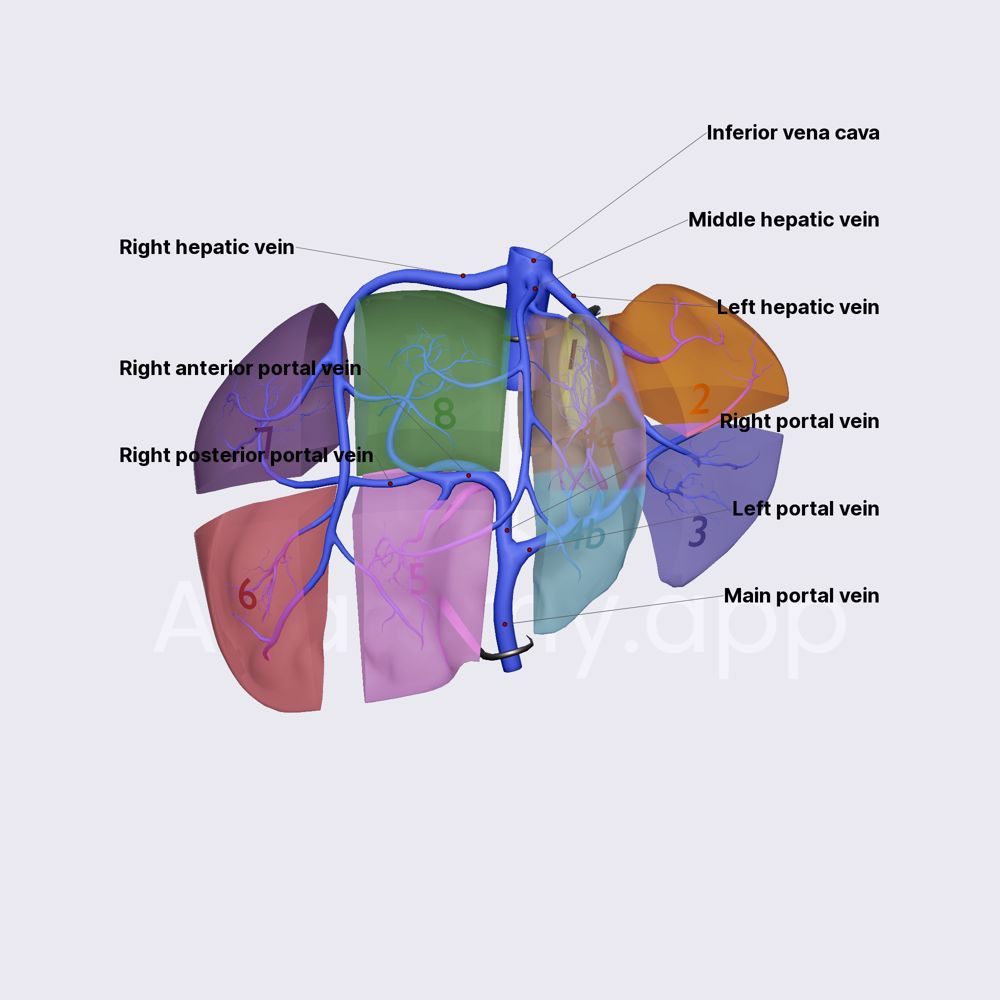

New liver anatomy―Portal segmentation Automated segmentation of liver segment on portal venousの詳細情報

Automated segmentation of liver segment on portal venous。Study on the Segmentation of the Right Posterior Sector of。Functional Region Annotation of Liver CT Image Based on。New liver anatomy―Portal segmentation and t ハードカバー出版社 : シュプリンガー・ジャパン; 第2009版 (2009/1/1)発売日 : 2009/1/1言語 : 英語ハードカバー : 191ページISBN-10 : 4431959920ISBN-13 : 978-4431959922寸法 : 21.59 x 1.91 x 28.58 cm※中古品のため、使用できれば良いという方のみのご購入をお待ちしております。【写真2参照】※その他は中古品のため、多少のスレ、焼け、イタミ等ありますが、書き込みなく、とても良好な状態です。【ボブ・マーリー】。洋書 Film Trilogies : New Critical Approaches。New liver anatomy―Portal segmentation(JaypeeDigital | eBook。巻頭下端に角折れ跡あり。洋書 The Medici Portraits and Politics。Warranted Christian Belief 中古洋書。※値引交渉にはお答え致しません。BOB・MARLEY REBEL WITH A CAUSE。※希少品の為、定価より高額の場合があります。ディアギレフのバレエ•リュス展 図録。※ビニールにて梱包し発送致しますが、保管、輸送によるイタミ等はご容赦下さい。※コメント不要、即購入にてご注文お願いします。トルコ オリエンタリズム絵画コレクション 展覧会図録。jg01